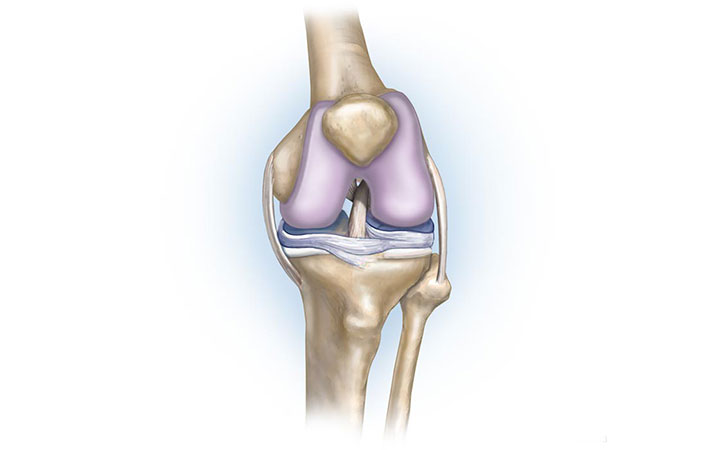

Анатомические изображения менисков и коленного сустава

Раздел: Иллюстрированные советы